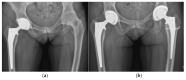

Osteoarthritis is a degenerative condition affecting the whole joint with the underlying bone, representing a major source of pain, disability, and socioeconomic cost worldwide. Age is considered the strongest risk factor, albeit abnormal biomechanics, morphology, congenital abnormality, deformity, malalignment, limb-length discrepancy, lifestyle, and injury may further increase the risk of the development and progression of osteoarthritis as well. Pain and loss of function are the main clinical features that lead to treatment. Although early manifestations of osteoarthritis are amenable to lifestyle modification, adequate pain management, and physical therapy, disease advancement frequently requires surgical treatment. The symptomatic progression of osteoarthritis with radiographical confirmation can be addressed either with arthroscopic interventions, (joint) preservation techniques, or bone fusion procedures, whereas (joint) replacement is preferentially reserved for severe and end-stage disease. The surgical treatment aims at alleviating pain and disability while restoring native biomechanics. Miscellaneous surgical techniques for addressing osteoarthritis exist. Advanced computer-integrated surgical concepts allow for patient personalization and optimization of surgical treatment. The scope of this article is to present an overview of the fundamentals of conventional surgical treatment options for osteoarthritis of the human skeleton, with emphasis on arthroscopy, preservation, arthrodesis, and replacement. Contemporary computer-assisted orthopaedic surgery concepts are further elucidated.